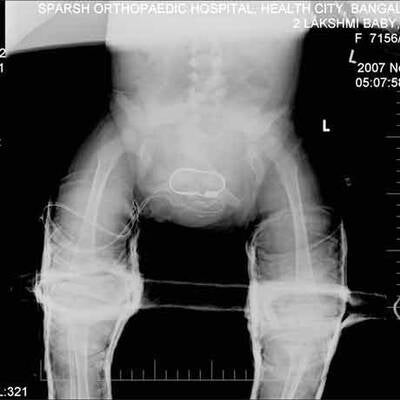

Knapp eine Woche nach einer Mammutoperation zur Entfernung von je zwei überzähligen Armen und Beinen hat sich das indische Mädchen Lakshmi am Dienstag erstmals der Öffentlichkeit gezeigt. Die Zweijährige lag im Arm ihres Vaters, hielt einen Keks in der Hand und schien gesund und aufgeweckt zu sein. Ihre Beine waren noch eingegipst. "Sie erholt sich sehr gut. Lakshmi ist jetzt nicht mehr in Gefahr", sagte Chefchirurg Sharan Patil in der südindischen Stadt Bangalore.

Sie reagiere gut auf die Behandlung und müsse daher nicht länger auf der Intensivstation bleiben, erklärte Patil. Lakshmi wurde am vergangenen Mittwoch operiert: 24 Stunden dauerte der Eingriff, 30 Ärzte waren daran beteiligt. Die Eltern des Mädchens zeigten sich danach überglücklich und erklärten, sie könnten endlich daran glauben, dass ihre Tochter ein normales Leben führen werde. Wann Lakshmi ihre Arme und Beine kontrollieren und laufen lernen kann, war aber noch unklar. Am Freitag kam das Kind wieder zu Bewusstsein. Das Mädchen habe gelächelt und die Zehen bewegt, erklärten die Ärzte. An den "neuen" Körper müsse sich Lakshmi aber offenbar noch gewöhnen.